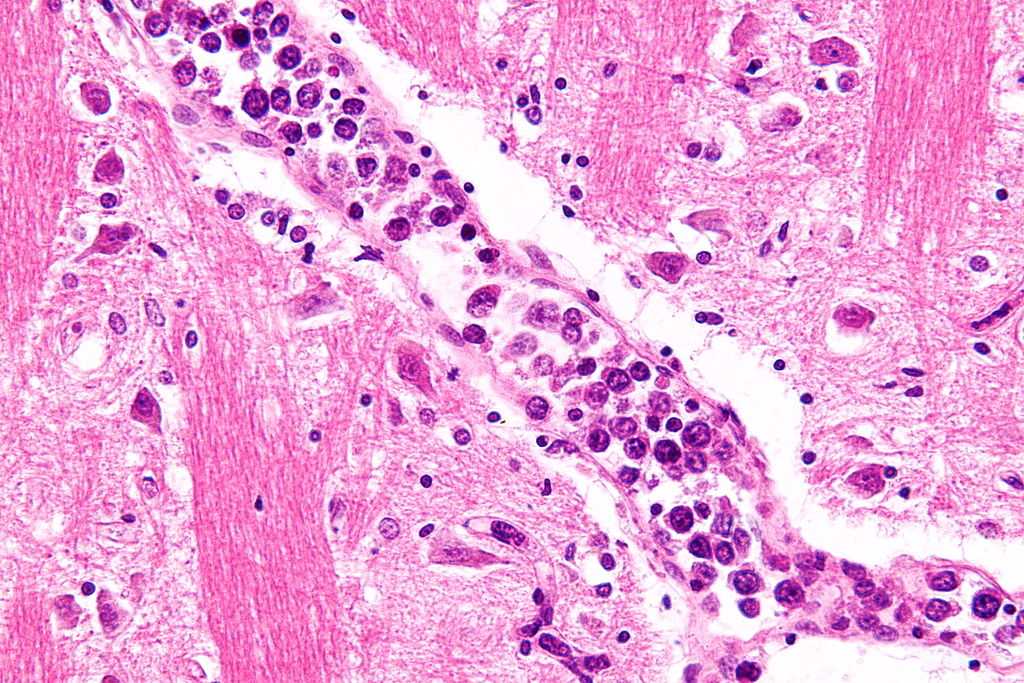

Το λέμφωμα εμφανίζεται συχνά σε παιδιά ή νεαρούς ενήλικες και χαρακτηρίζεται από την ανεξέλεγκτη επέκταση των κυττάρων του ανοσοποιητικού μας συστήματος που ονομάζονται λεμφοκύτταρα, προκαλώντας μεγάλες μάζες ιστού που συχνά παραμορφώνουν τους ασθενείς. Αυτός ο καρκίνος συνήθως αντιμετωπίζεται με χειρουργική αφαίρεση των μαζών του όγκου και στη συνέχεια, στις περισσότερες περιπτώσεις, με χημειοθεραπεία, με υψηλά ποσοστά ύφεσης, πάνω από 80% στα παιδιά.